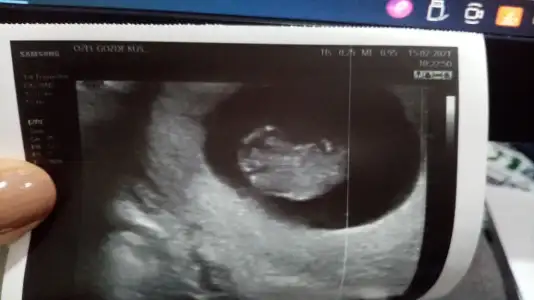

• IMG-20210215-WA0012.webp

IMG-20210215-WA0012.webp

21,7 KB · Görüntüleme: 55

Bakabilir ısın cok tesekkür ederim kız mı erkek ı Ay cok heyecanlı🧚‍♂️